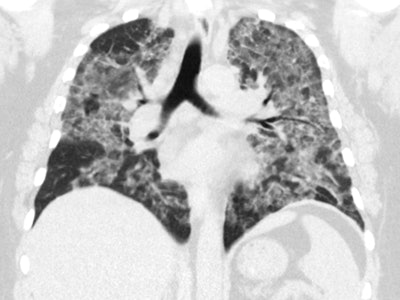

After examining at least 65 EVALI cases in just the past several months, Kligerman and colleagues at UCSD recognized four patterns on chest x-ray and CT scans that appeared more often than the rest:

- Organizing pneumonia: By far the most common imaging pattern, organizing pneumonia is marked by bilateral ground-glass opacity with mild consolidation, septal thickening (including a "crazy paving" pattern), and striking subpleural and perilymphatic sparing, often in the central portions of the lung around the heart. Most EVALI predominantly affected by organizing pneumonia tend to recover quickly after steroid treatment.

Diffuse alveolar damage: Diffuse alveolar damage is similarly characterized by ground-glass opacities, perilymphatic sparing, and septal thickening, but the pattern is associated with a relatively higher mortality rate. In some instances, follow-up imaging two weeks after initial diagnosis showed subpleural blebs near regions of the lung that were being destroyed, resulting in permanent fibrosis. Many of these patients ended up dying a few weeks later, despite steroid treatment.